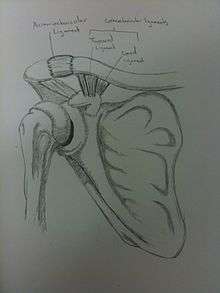

The acromion of the scapula is connected to the clavicle by the superior acromioclavicular ligament. The coracoclavicular ligaments connect the clavicle to the coracoid process. The two ligaments that form the coracoclavicular ligaments are the trapezoid and conoid ligaments. These three ligaments add support to the shoulder joint.